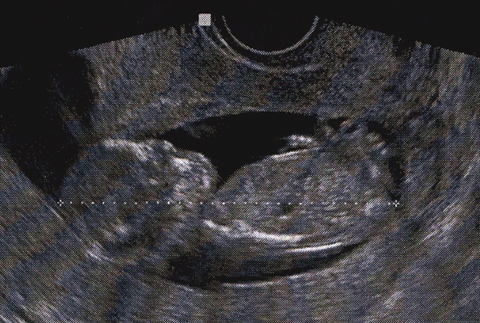

Say hello to the little one!

The ultrasound was wonderful – everything looked good. The baby was moving around SO much in there! I can’t believe I can’t feel it. Matt and I were both surprised since we’re so used to seeing still u/s photos. I figured it would move its arms a little, but it was moving its whole body a ton. The tech needed the baby to get into a certain position for the NT test, and it took a good 30 minutes of wiggling my uterus around to get it there. The baby is a stubborn little one who wanted maximum attention from the outside world!

Check out this shot of the paw! Don’t worry – there are 5 fingers. The thumb was tucked!